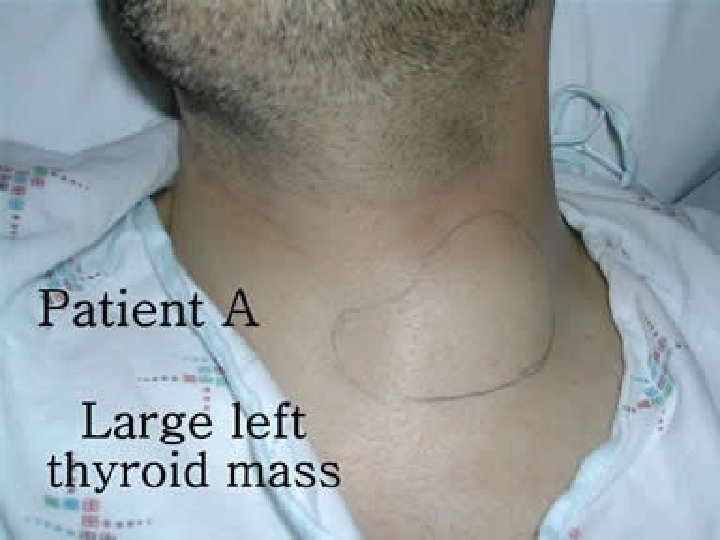

Primary malignant lymphoma of the thyroid Accounts for <5% of all thyroid malignancies and is primarily treated with chemotherapy and external beam radiation. With the advent of modern immunophenotypic analyses, fine-needle aspiration (FNA) can potentially obviate the need for surgical procedures